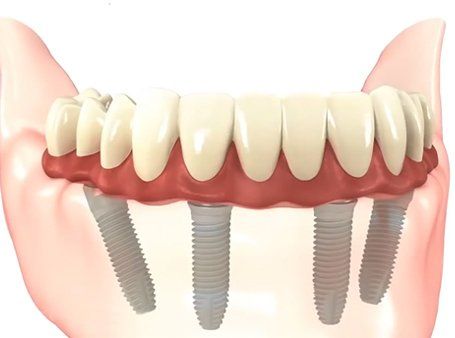

Realizzazione di impianti dentali"All on four" (on five, on six)

La "All on four" è una tecnica a carico immediato di implantologia dentale, studiata per gli edentuli quindi per persone che purtroppo hanno perso tutti o quasi tutti gli elementi dentali presenti in un'arcata.

Può essere eseguita sia nell'arcata dentale superiore che nell'arcata dentale inferiore sempre che le condizione ossee lo rendano possibile, è per questo motivo importante fare un analisi radiografica dettagliata tridimensionale Conebeam.

Grazie ad "All on four" persone costrette alle protesi totali mobili in resina e superiori con palato, possono godere di una nuova dentatura fissa e poco ingombrante.